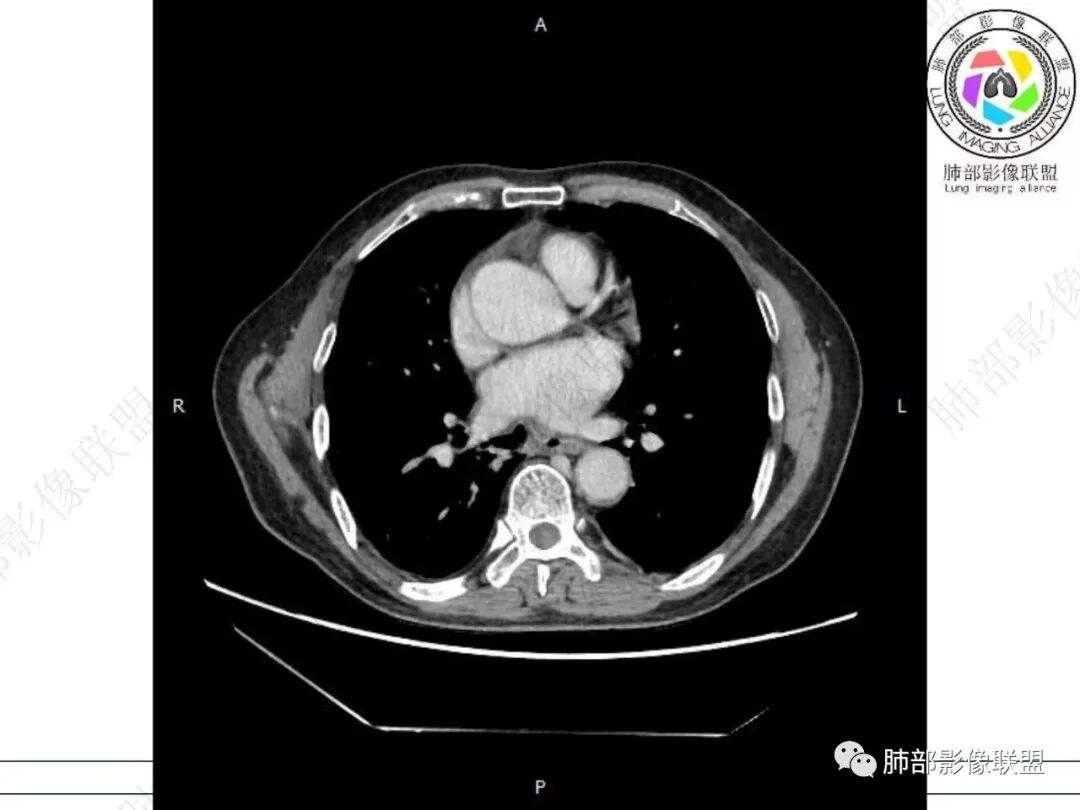

气管隆突下团片影,其内积气,与食道分界不清,食道壁增厚,管腔狭窄,右下肺实变影,支气管壁增厚,考虑食管支气管瘘并右下肺感染,食道肿瘤病变不除外

支持食管支气管瘘(考虑食管癌)伴后纵隔及右肺感染,食管管壁明显增厚,管腔狭窄,相邻右侧后纵隔内软组织内可见气体影,与食管分界不清,右肺有实变及不张。

右肺下叶背段条片状实变影,内可见支气管走行,支气管有狭窄有扩张,周围可见磨玻璃影,隆突下团片影,内密度不均可见气体影,与周围结构界限不清。食管下段壁增厚,管腔狭窄,右肺下叶慢性炎、肺不张,考虑食道肿瘤所致气管食管瘘。

老年男性,慢性病程,右肺下叶斑片影、斑点影、实变影,支气管轻度扩张,病灶整体稍收缩;食道壁增厚、肿胀、模糊,气管隆突及右后纵隔旁见软组织块影,其内见气泡影,均匀强化,符合食道支气管瘘伴周围炎症,右下肺炎症

右肺下叶沿肺叶肺段分布斑片、条片状影,以下叶背段为显,边缘模糊,内可见支气管走行,局部支气管管壁增厚,右侧胸腔少量积液。纵隔隆突下可见不均匀软组织密度影,与周围结构分界不清,内见气体密度影,与食管及相邻右肺支气管之间未显示通道。邻近食管下段壁明显不规则增厚,增强后食管管壁明显不均匀强化,可见线样强化的连续完整粘膜影。

右肺下叶片影,气道相关,符合感染性病变。纵隔隆突下软组织密度影,异常气体影,长病程,起病缓慢,提示存在气管或食管瘘。食管镜未见明显新生物形成,临床未提供进食或饮水呛咳临床表现,综合分析应该考虑支气管瘘的形成。

对比患者3月份的CT图,原隆突下存在增大钙化淋巴结,现在出现气体影,且钙化显示不清,应想到淋巴结结核破溃成瘘可能性。